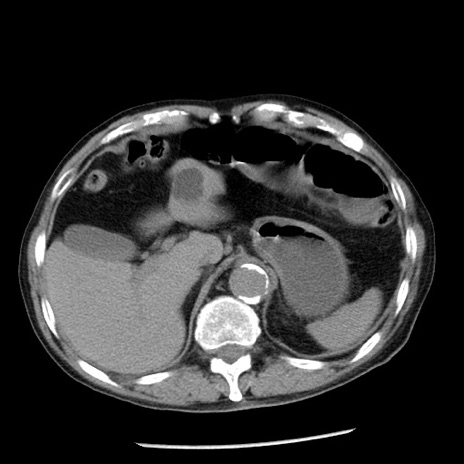

冠状断像

【症例】80歳代男性

【主訴】嘔吐

【現病歴】昨晩2回嘔吐あり、今朝になっても嘔吐あり。来院。

【既往歴】胃潰瘍

【身体所見】意識清明、BT 37.6℃、BP 166/95mmHg、HR 100bpm、SpO2 97%、腹部:平坦・軟、腸蠕動音聴取良好、圧痛なし。

【データ】WBC 21900、CRP 1.46